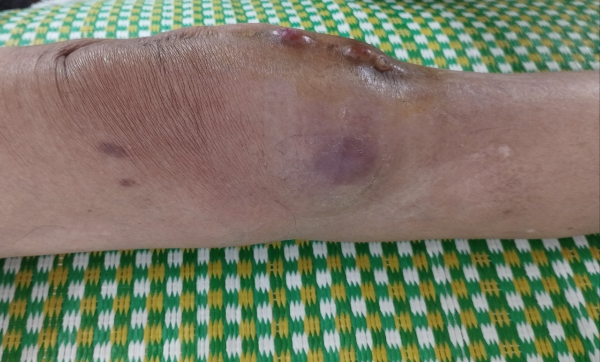

– Tại chỗ:

+ Khớp gối phải sưng nề vừa, phía trướ khớp gối viêm nề, hơi đỏ

+ Sẹo mổ mặt trước gối dài 20cm có 2 vị trí nhỏ trên vết mổ chảy ít dịch vàng đục, hơi sệt, phía ngoài gối có một ổ abces giai đoạn viêm đỏ.

Hình 1. Hình ảnh tổn thương tại chỗ khớp gối